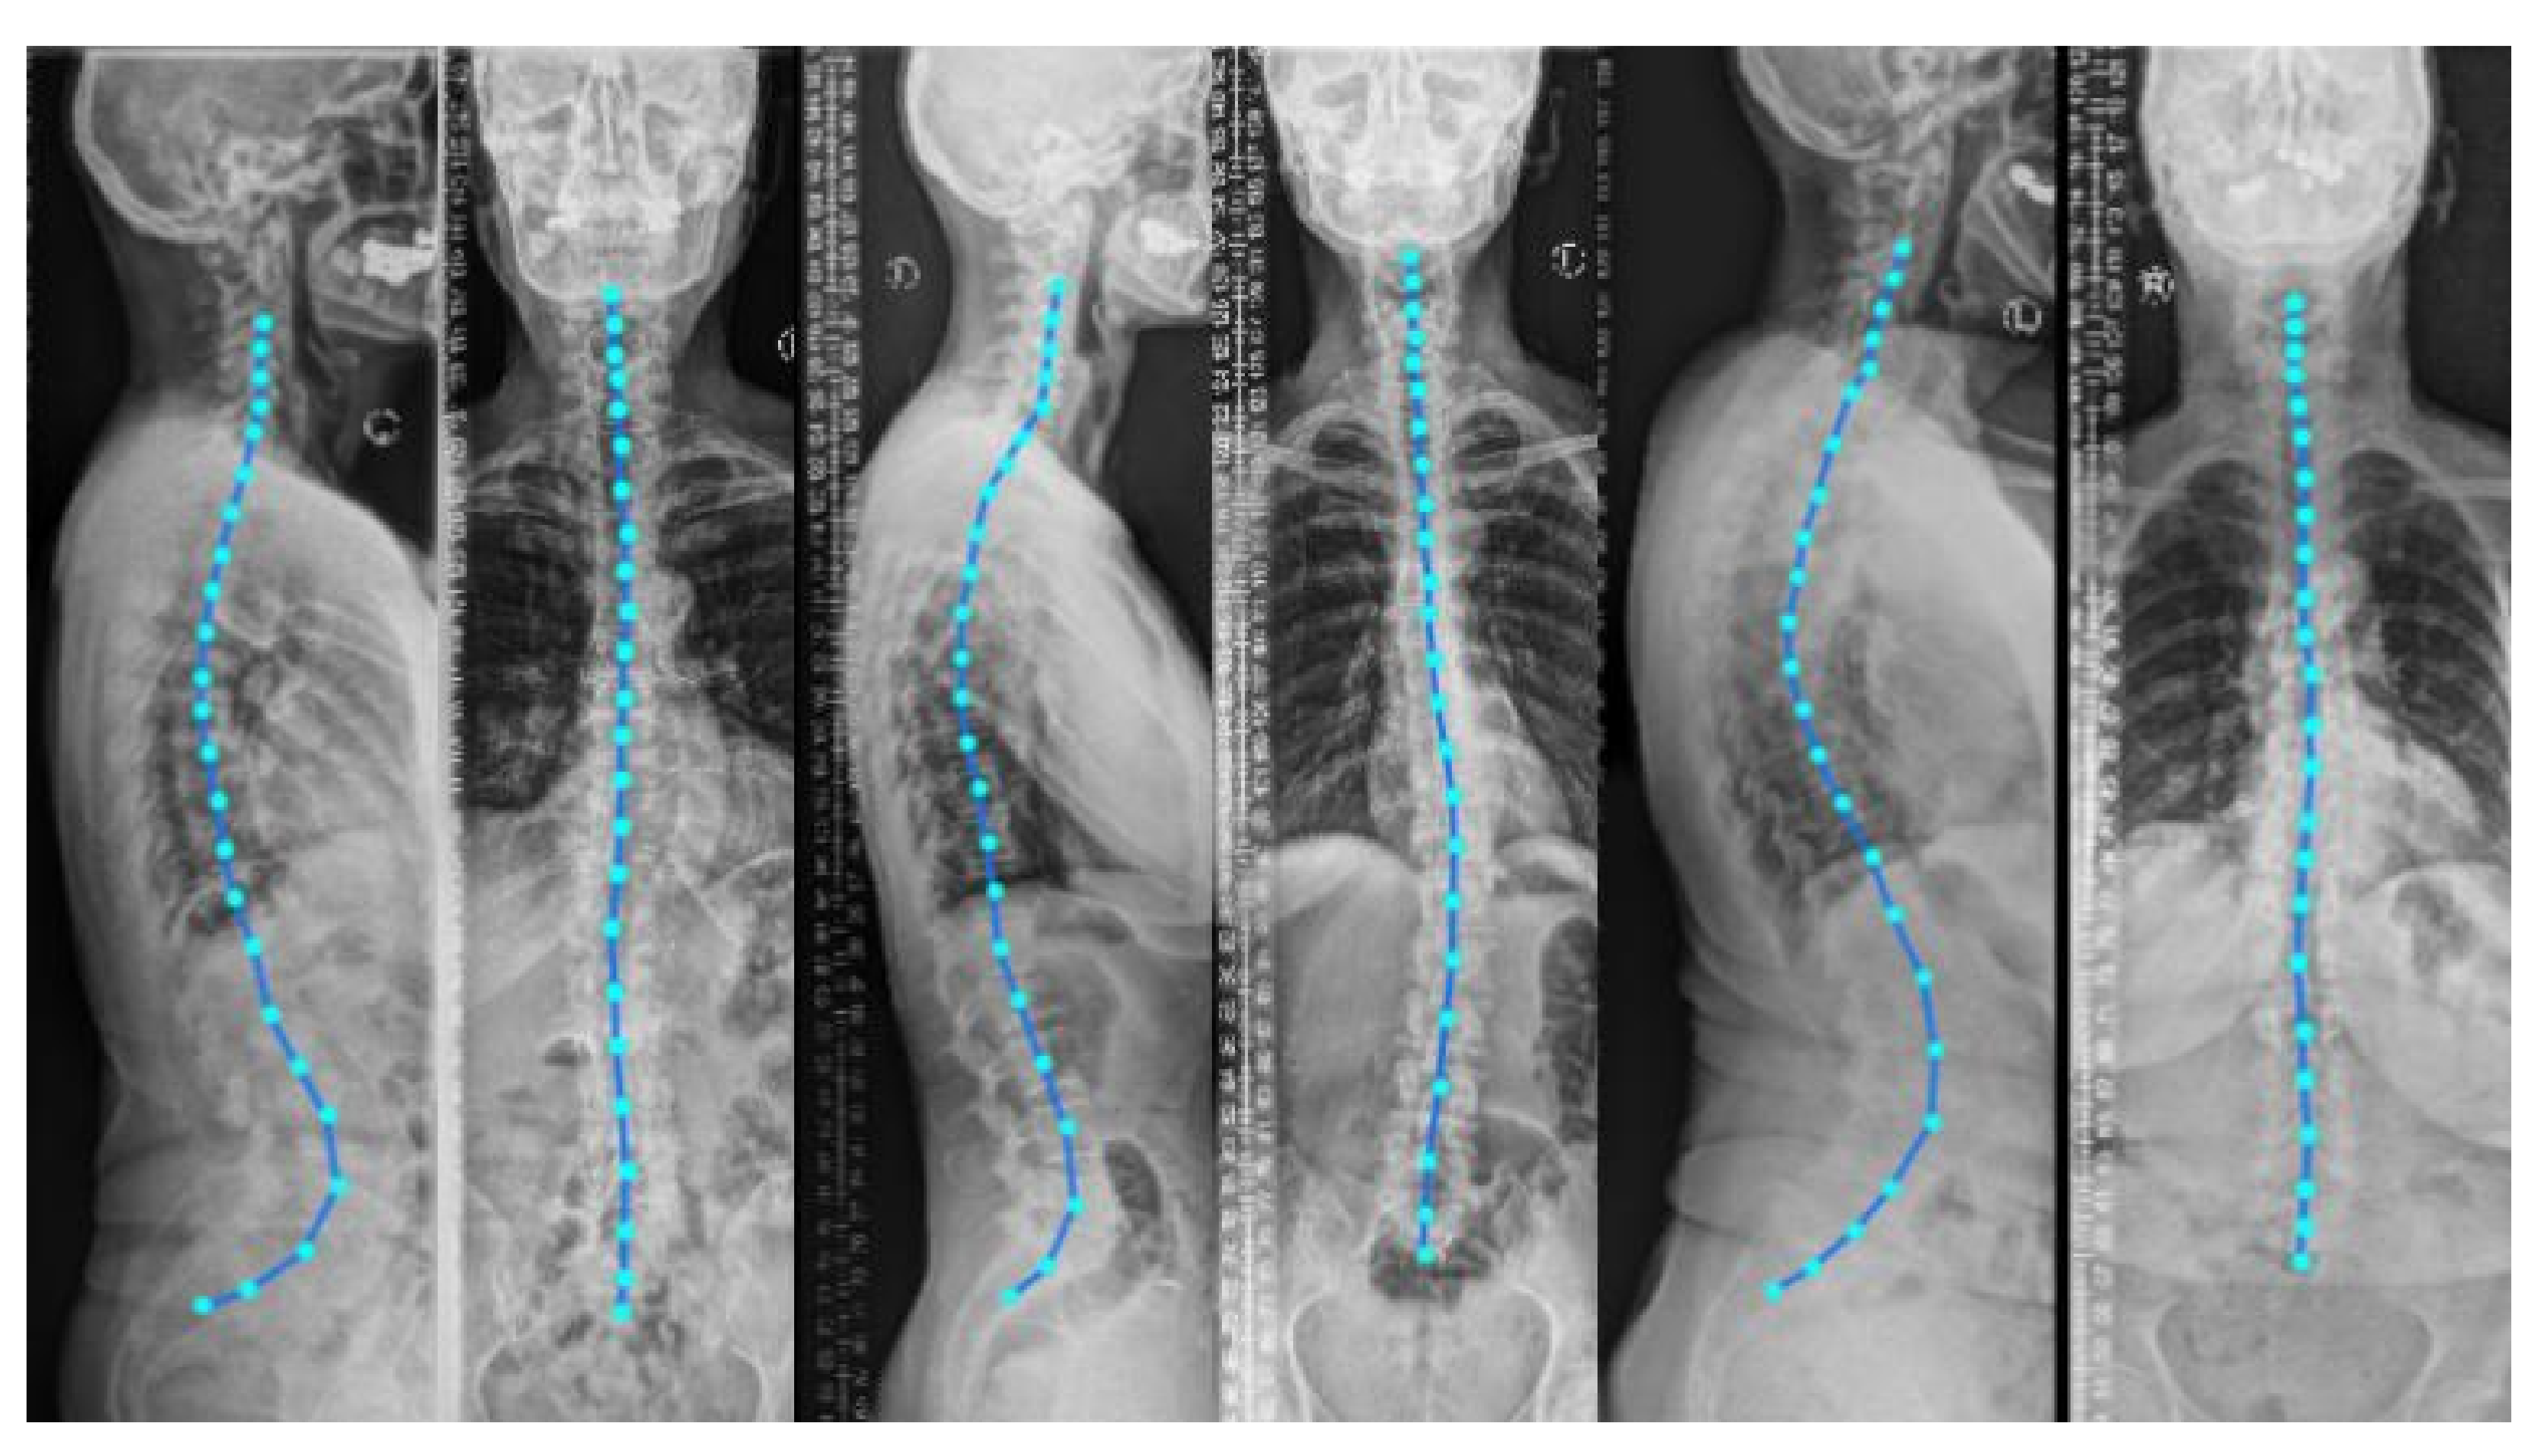

A biomechanical load analysis of the spine in an upright standing position is highly warranted in various spine disorders to understand their cause and guide therapy [1]. Typical approaches for load estimation either use a computational shape model of the spine for all patients or obtain a subject-specific spine model from a 3D imaging modality such as magnetic resonance imaging (MRI) or computed tomography (CT) [2]. Even though MRI and CT images can capture 3D anatomical information, they need the patient to be in a prone or supine position (lying flat on a table) during imaging. Nevertheless, to analyze the spinal alignment in a physiologically upright standing position under weight bearing, orthogonal 2D plain radiographs (as depicted in Figure 1) are the de facto choice. A combination of both these worlds is of clinical interest to fully assess the true biomechanical situation, that is, to capture the patient-specific complex pathological spinal arrangement in a standing position with full 3D information [2,3,4].

Including the vertebral centroid coordinates in the global coordinate system provides the model with a holistic shape of the spine. For example, Figure 1 demonstrates lateral and anterior–posterior (AP) view radiographs of three different patients. The distance between the centroids determines the scale. If one fits a curve to all of the vertebral centroids, the orientation of each vertebra should be almost perpendicular to the curve at each vertebral centroid. Although defining the orientation of the vertebrae and the other constraints, such as inter-vertebral distance, needs accurate vertebral landmark detection on radiographs, we postulate a Multi Layer Perceptron (MLP) which estimates the 3D affine parameters, given only the vertebral centroids and the information extracted by the encoders.

Figure 1. Lateral and anterior-posterior (AP) view radiographs of three patients with spinal curvature annotation. Considering the vertebral centroid coordinates and spinal curvature facilitates determining the scale and the vertebral orientation.